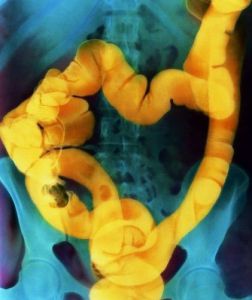

Ирригоскопия — рентгенологическое исследование толстой кишки при ретроградном заполнении ее рентгеноконтрастной взвесью.

Ирригоскопия применяется для уточнения диагноза заболеваний толстой кишки (пороки развития, опухоли, хронический колит, дивертикулез, свищи, рубцовые сужения и др.).

Ирригоскопия дает возможность получения информации о морфологических изменениях толстой кишки, что в плане диагностики нозологических форм представляется более ценным. Ирригоскопия нередко является решающим методом диагностики опухолей, дивертикулов толстой кишки. Увеличивает диагностические возможности ирригоскопии методика двойного контрастирования. В отношении таких заболеваний как колиты, туберкулез могут быть получены лишь косвенные признаки.

Под рентгенологическим контролем постепенно заполняют рентгеноконтрастной взвесью толстую кишку и производят обзорные и прицельные снимки всех ее отделов в разных положениях больного. На следующем этапе, после удаления из толстой кишки рентгеноконтрастной взвеси, исследуют рельеф слизистой оболочки кишки.

На заключительном этапе ирригоскопии, особенно при подозрении на опухоль толстой кишки, исследование проводят при дозированном заполнении кишки воздухом, используя аппарат Боброва (двойное контрастирование).